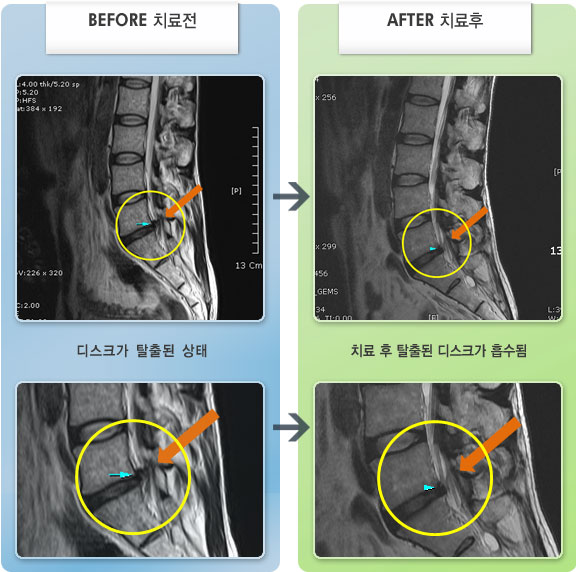

저는 교통사고 후유증과 운동부족,잘못된 자세등으로 간혹 허리가 아팠습니다.. 근데 최근 몇일간 무리한후에 허리가 아프고 왼쪽 하지방사통과 저린감이 너무 심하여 밤에 잠도 제대로 들기 어려울 정도 였습니다...MRI를 찍으니 디스크라고 하더라구요..ㅠ..ㅠ 예상은 하고 있었지만 20대후반에 디스크라니...좌절감과

우울감이 심하였습니다.. 무조건 수술은 안하리라는 생각에 원장님을 찾아뵈었습니다..저한테는 어떻게보면 행운이였나봅니다...

앞으로 치료계획에 대해 상세히 설명해주시며 믿음과 희망을 주셨습니다 ..마음이 한결 가벼워 졌습니다..

추나, 침, 약침, 물리치료, 약물(한약)요법을 병행하며 현재 2주가 조금 지났는데...저도 놀랄정도로 왼쪽 하지방사통은 거의 없어졌어요..감동감동 ㅠ..ㅠ

치료에 대해 믿음이 있었지만 이렇게 빨리 회복이 될지는 저도 놀랐습니다...